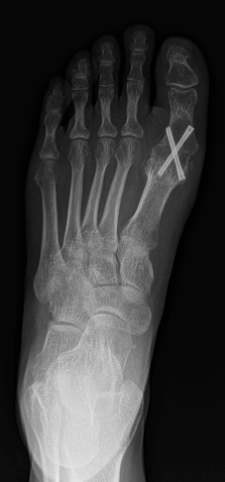

Indien de slijtage in het gewricht te ver gevorderd is, dan is de enige goede operatieve oplossing het vastzetten van het grote teen gewricht. Dat noemen we een arthrodese. Hierbij nemen we alle zieke kraakbeen weg en zetten de botten tegen mekaar vast met schroeven (soms plaat en schroeven). Na de ingreep krijg je 2 weken steunverbod in een spalk, nadien nog 4 weken bescherming in een speciale loopschoen die je vanuit het ziekenhuis reeds meekrijgt. 6 Weken na de ingreep is er een RX-controle om te bevestigen dat het bot goed is vastgegroeid. De totale revalidatie duur van een arthrodese bedraagt 2 tot 3 maanden tot je weer heel vlot alle activiteiten kan doen inclusief sporten.